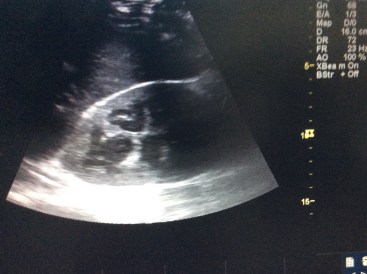

Slowly, over the course of several months, things kept getting worse for Jim as one organ system after another started to fail. He developed a large pericardial effusion (fluid around his heart – cover photo), Bell’s Palsy (paralysis of his facial muscles), Pancytopenia (low blood counts), hydronephrosis (extra fluid in his kidneys) and a large cystic lesion in his liver. The bone marrow sample fortunately (and unfortunately) did not show Leukemia. I frequently discussed his symptoms with other more experienced doctors, particularly Dr. Bill, one of the smartest doctors I have known. We sent his list of ailments along with pictures to doctors at the Mayo clinic. His list of problems kept on growing and we did not have any answers. We tried what we could—TB medicine, antibiotics, steroids, cardiac meds—but nothing helped.